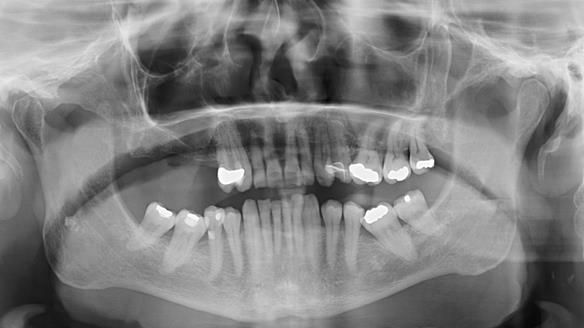

Welcome to Newsletter 64. I'll walk you through the process of providing a Mk 2 metal-based partial denture (RPD), for Ian a retired Veterinary Surgeon aged 78. The RPD was made at an increased vertical dimension and acted as an occlusal stabilisation splint - reducing the wear and bite force on the remaining natural teeth.